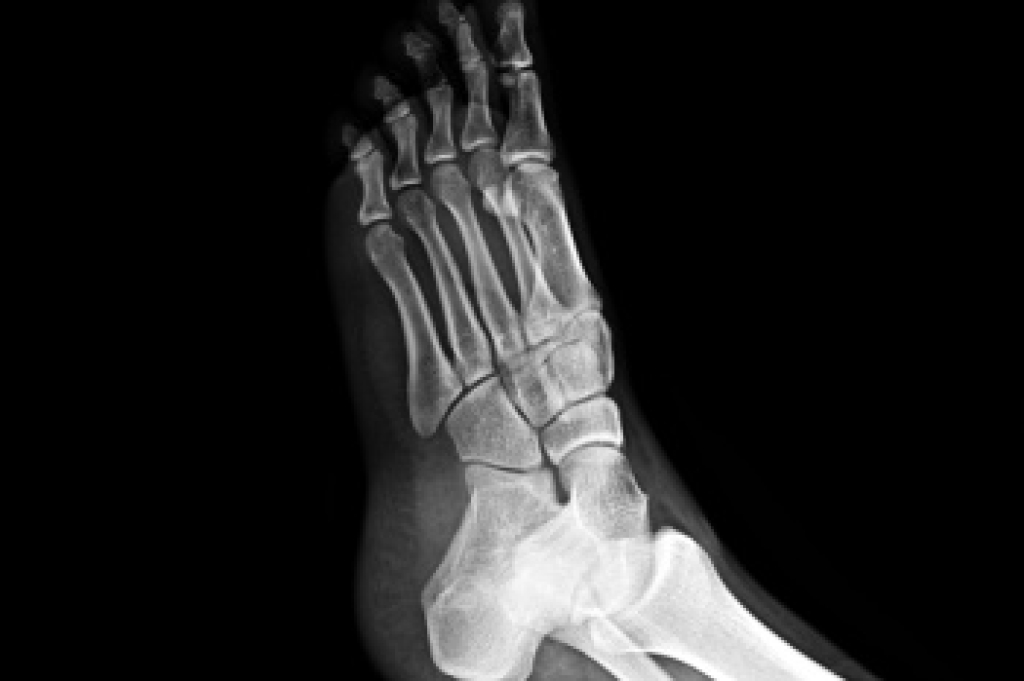

Hammertoe is a foot deformity that occurs due to an imbalance in the muscles, tendons, or ligaments that normally hold the toe straight. It can be caused by the type of shoes you wear, your foot structure, trauma, and certain disease processes.

If you have hammertoe, you should change into a more comfortable shoe that provides enough room for your toes. Exercises such as picking up marbles may strengthen and stretch your toe muscles. Nevertheless, it is important to seek assistance from a podiatrist in order to determine the severity of your hammertoe and see which treatment option will work best for you.